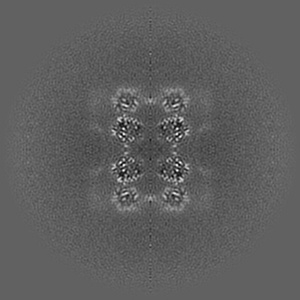

Human p97/VCP structure with a triazole inhibitor (NSC799462/dodecamer)

Single-particle3.33 Å

Sample: p97/VCP AAA+ ATPase/NSC799462

Mechanism of allosteric inhibition of human p97/VCP ATPase and its disease mutant by triazole inhibitors.

(2024) Commun Chem , 7 , 177 - 177